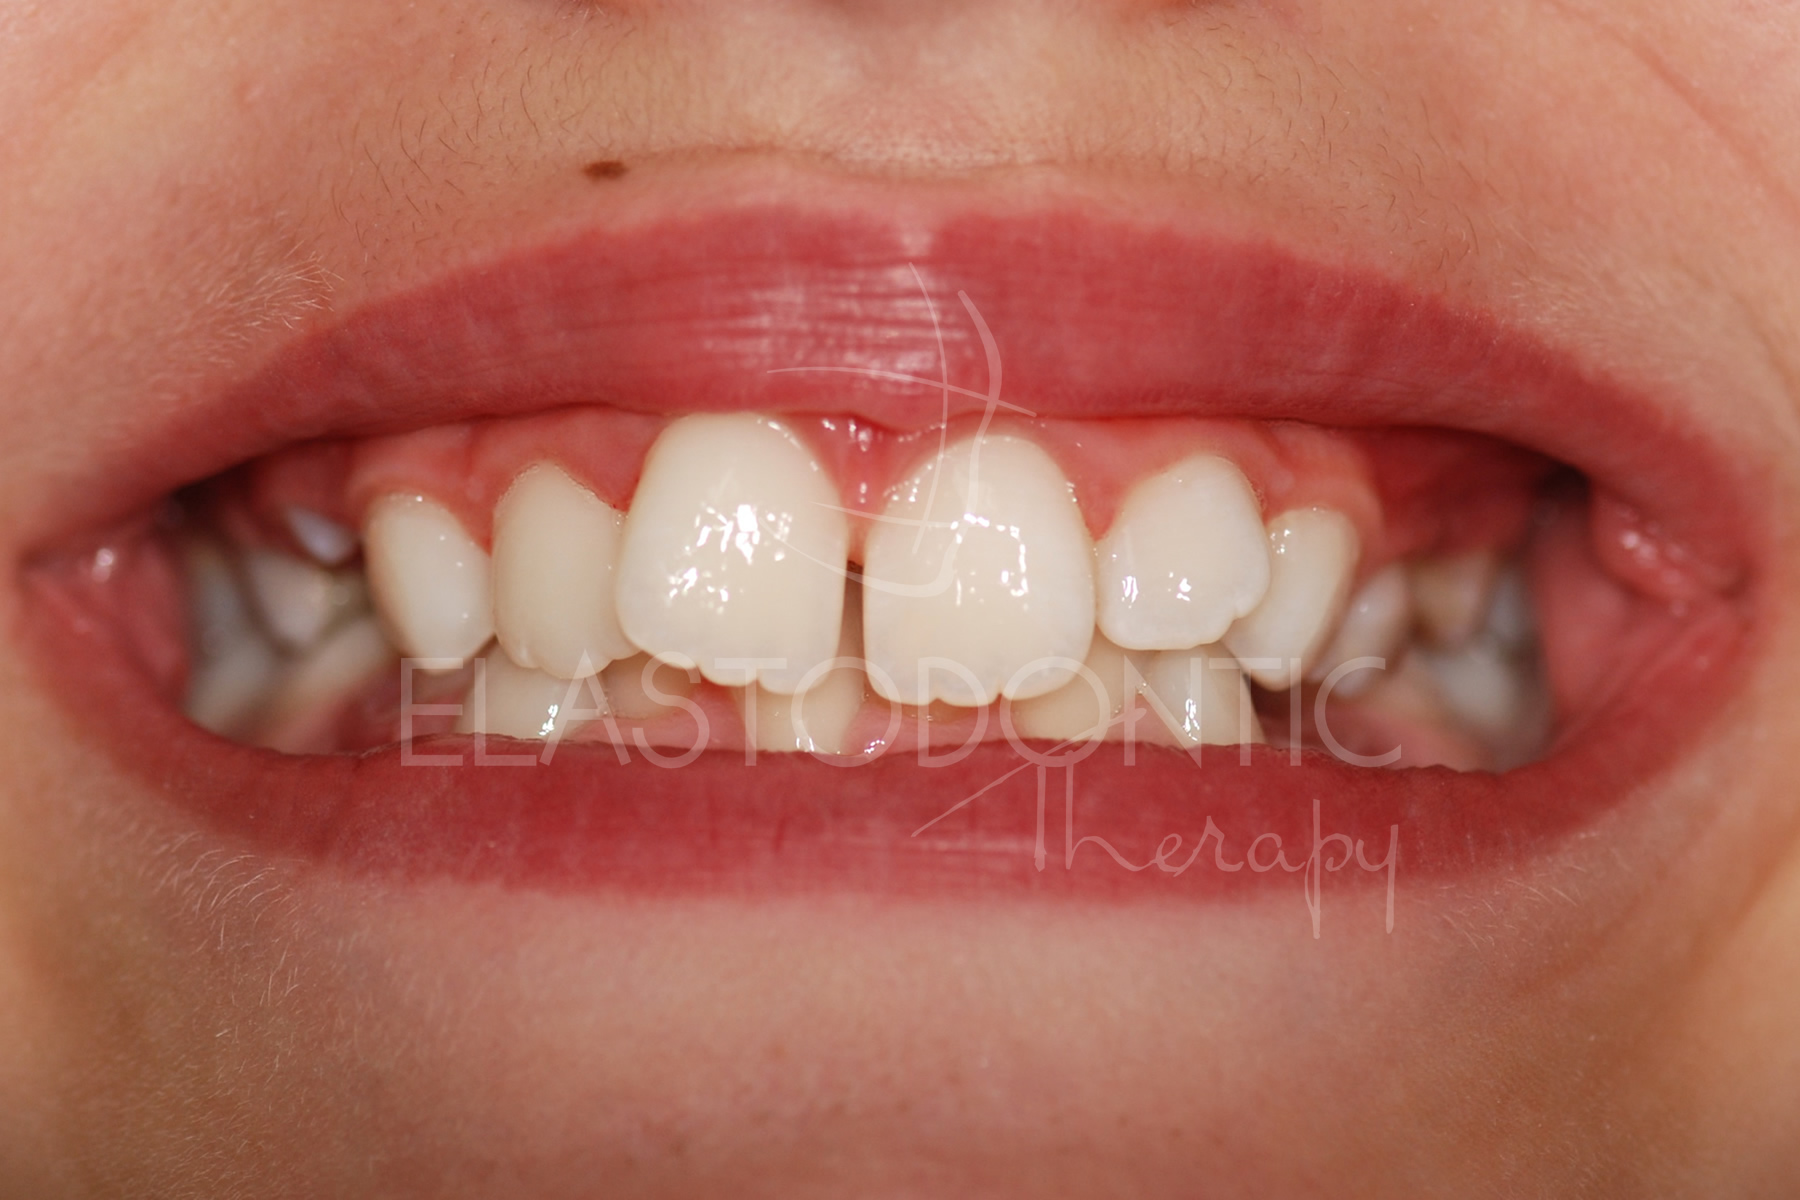

L'Elastodontic Therapy® iniziata all'età di 9 anni, ha permesso di correggere la malocclusione in pochissimi mesi con l'ausilio di un SOLO apparecchio elastodontico e cosa importante senza ricorrere ad estrazioni che avrebbero compromesso il risultato estetico della terapia.

La stabilità nel tempo è garantita dal raggiungimento di un ottimo rapporto occlusale fisiologico e biologicamente determinato.